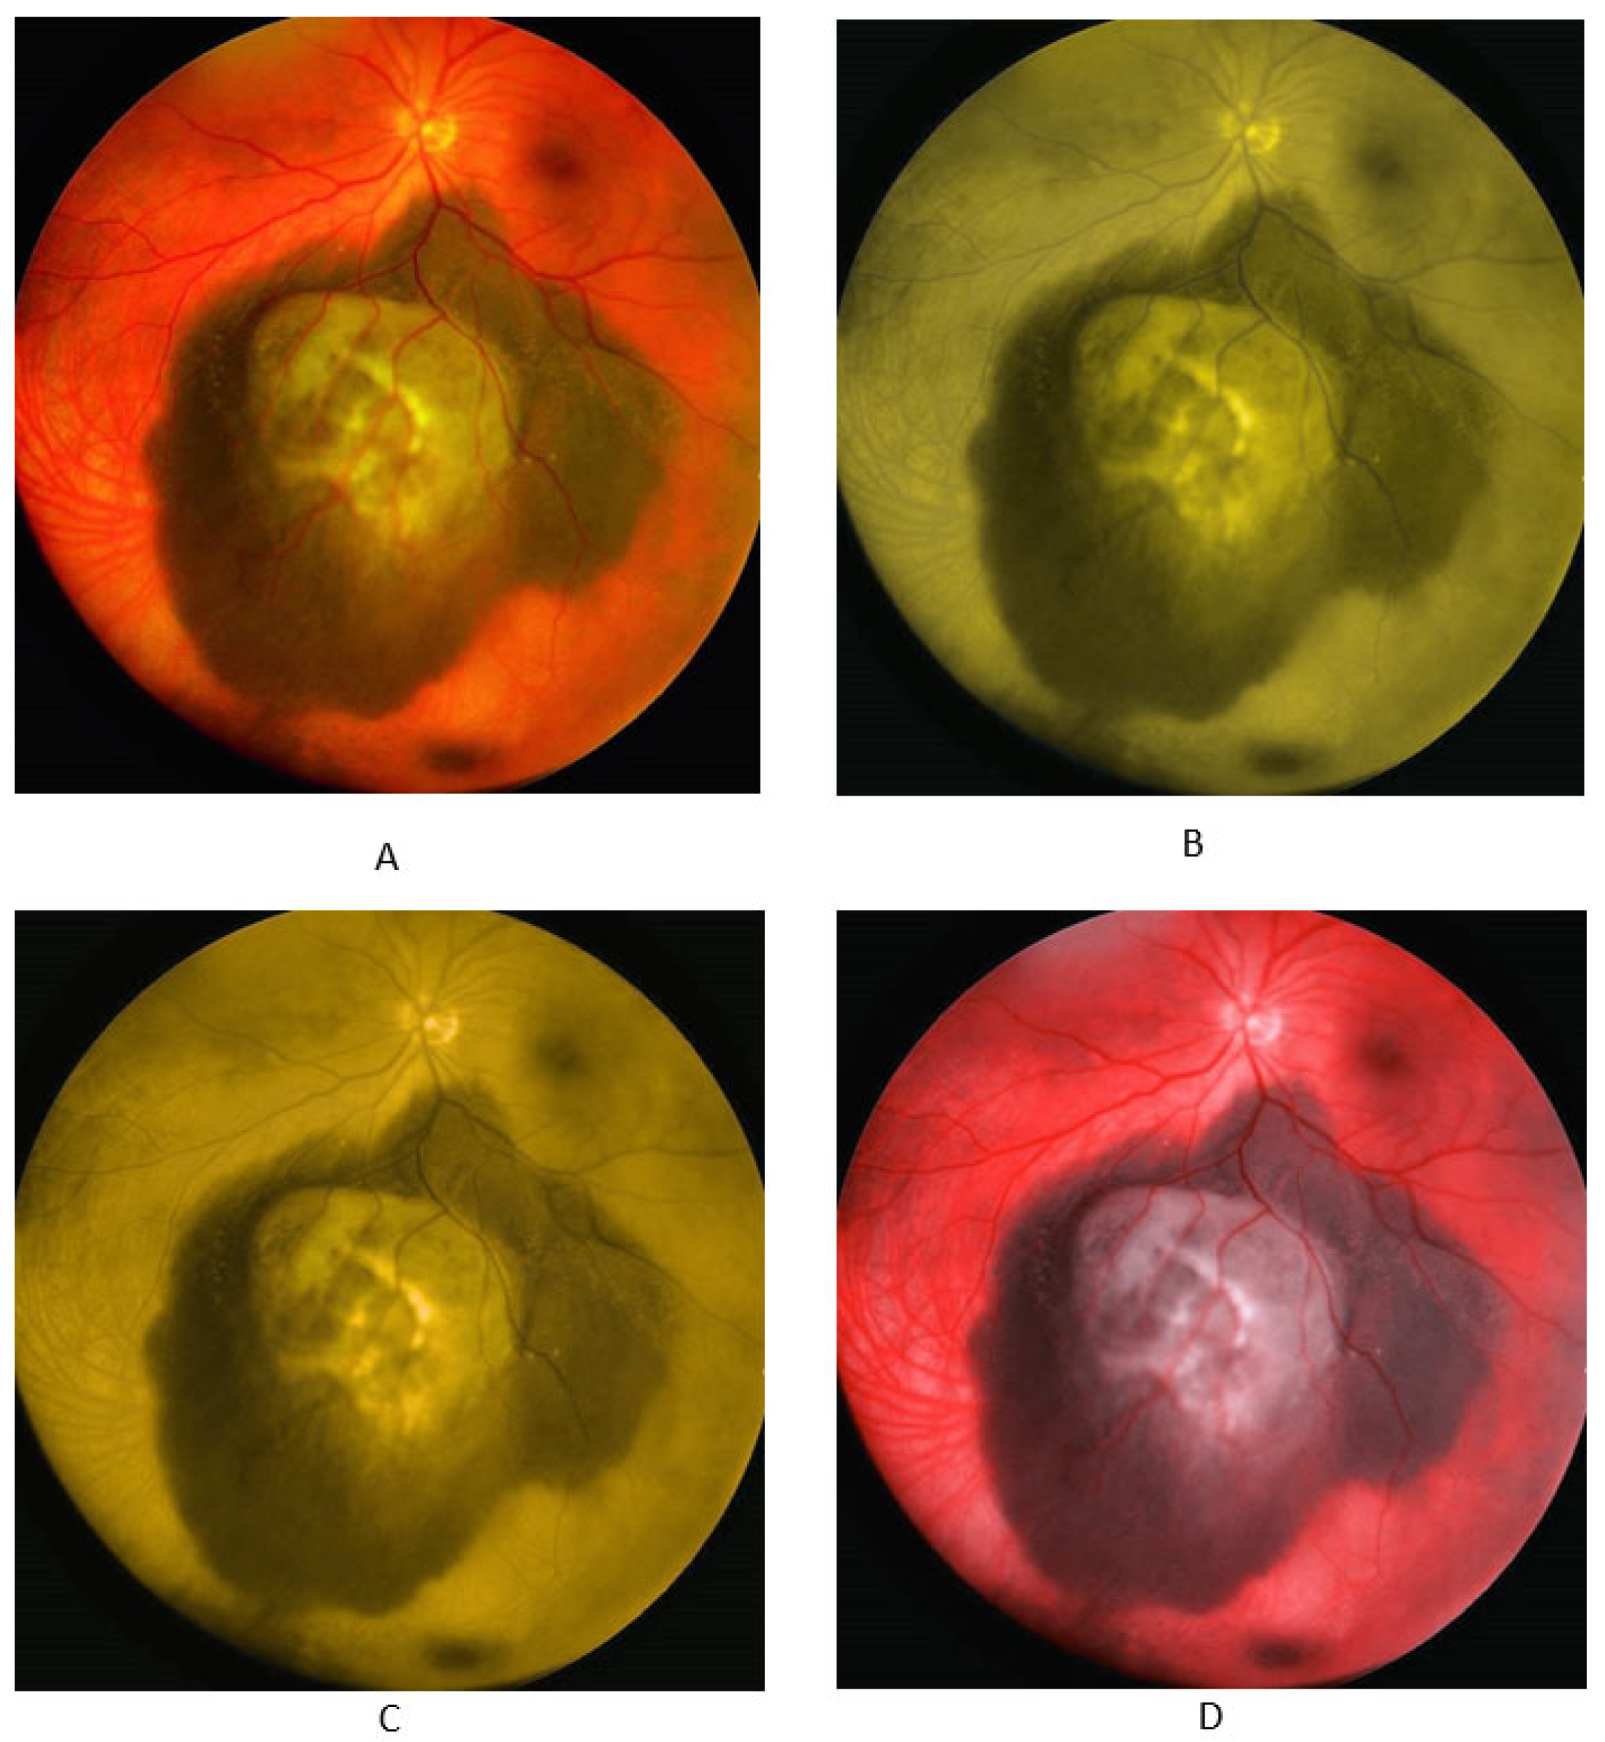

3.1. Melanoma Images